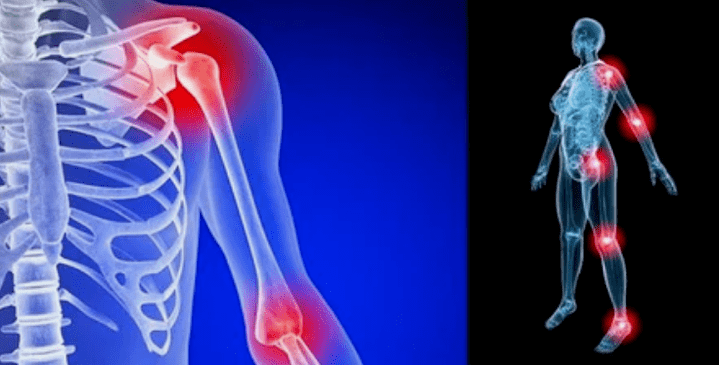

Die Manifestationen der Krankheit unterscheiden sich in Abhängigkeit von der Lokalisierung kaum, häufiger spiegeln sich die Zeichen auf den Knie-, Schulter- und Hüftfugen aufgrund einer hohen Belastung wider.

Die Ursachen der Arthrose der Gelenke unterscheiden sich in Abhängigkeit von der Form der Pathologie. Die Verformung der Arthrose des Ellbogengelenks, des Knöchelgelenks und der Schulterarthrose entwickelt sich manchmal ohne merkliche Ursachen. Es ist möglich, sie mit einem Arzt, einem Spezialisten für Rheumatologie, zu erkennen. Wenn dem Problem nicht sichtbare Pathologien vorausging, wird die Krankheit als primär bezeichnet. Die sekundäre Form des Verstoßes wird hauptsächlich diagnostiziert und kann verschiedene Staaten provozieren.